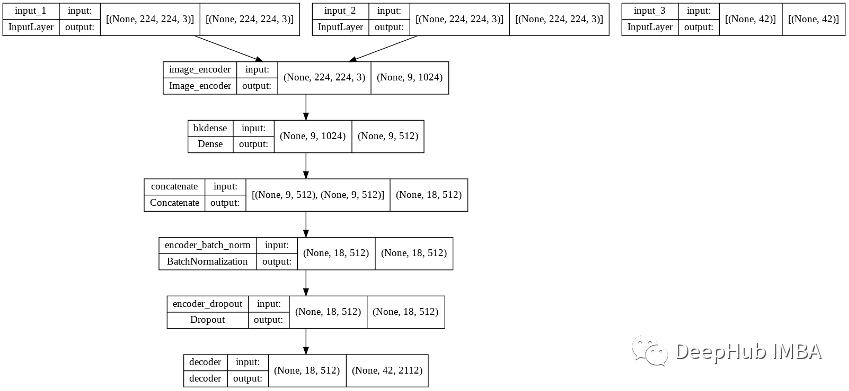

我们的模型结构如下:

训练的参数如下:

batch_size = 100

embedding_dim = 300

dense_dim = 512

lstm_units = dense_dim

dropout_rate = 0.2

lr (Learning Rate) = 10**-2

number of epochs = 10

min_lr (Minimum Learning rate) =10**-7